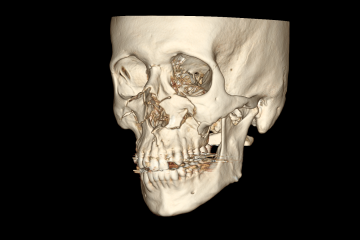

O maxilar quebrou em várias partes em ambos os lados da face. A parte da arcada dentária se soltou do crânio, ela recuou 7mm. Era visível a deformação, dava para sentir ela se acomodar quando eu falava.

Fiquei internado uma semana, a cirurgia para fixação dos ossos foi realizada com sucesso.

Essas são imagens da minha tomografia.